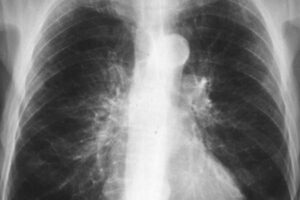

Как выглядят легкие при бронхите на флюорографии

Бронхит — распространенное заболевание с множеством причин, что связано с разнообразием его клинических симптомов. Часто бывает необходимо дифференцировать его от других, более серьезных заболеваний. Для этого используются рутинные методы нейровизуализационного исследования, в частности флюорография и рентгенография, а также компьютерная и магнитно-резонансная томография, бронхоскопия. Эти методы не только показывают, как выглядит бронхит, и позволяют отличить его …

TNM классификация рака легкого

В настоящее время рак больше не приговор, современная медицина научилась с ним бороться, но еще не побеждена. Большое значение в прогнозе неопластических заболеваний имеет степень дифференцировки клеток, которая отражает злокачественность новообразования, а также степень распространения процесса. Эти критерии учитываются международной классификацией TNM G, имеющей принципиальное значение при определении тактики лечения и прогноза при заболевании. Классификация …